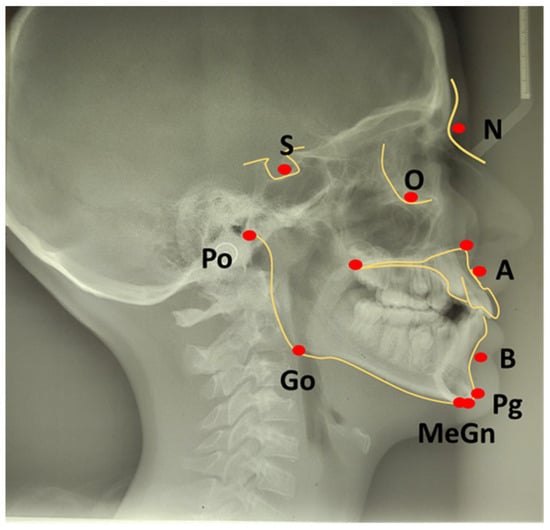

- SNA angle is formed between points of center sella turcica (S) and nasion (N) as the most anterior point of frontonasal suture, and subspinal point of deepest spot of contour of premaxiila (A), which presents the position of maxilla anteriorly or posteriorly to the cranial base. An average value of SNA angle is 80° ± 2°, while a higher value shows that the maxilla is protrusive, and a lower value indicates that the maxilla is more retrusive than normal;

- SNB angle is formed by connecting points of center sella turcica (S) and nasion (N) as the most anterior point of frontonasal suture, and the point that presents the deepest spot of the mandible (B). The average value of SNB is 78° ± 2°. A value above indicates that the mandible is more anterior to the cranial base, or protrusive, and a value below is a more backward, retrusive position;

- ANB angle is the angle between point A-N-B or the difference between SNA and SNB angle, with a normal discrepancy between maxilla and mandible ± 2°. A higher value points to the angle class II malocclusion relationship, while a lower angle indicates the angle class III malocclusion (Figure 2).